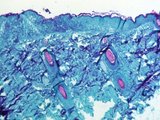

Thời gian ủ bệnh của đậu mùa khỉ là từ 5 đến 21 ngày nên mọi người được cảnh báo là phải cẩn trọng trong 3 tuần sau khi phơi nhiễm hoặc phát hiện mắc bệnh. Các triệu chứng ban đầu gồm sốt, nhức đầu, sưng hạch bạch huyết, đau lưng và cơ, tiếp đó là xuất hiện phát ban với mụn mủ trên mặt, tay và các bộ phận khác trên cơ thể.